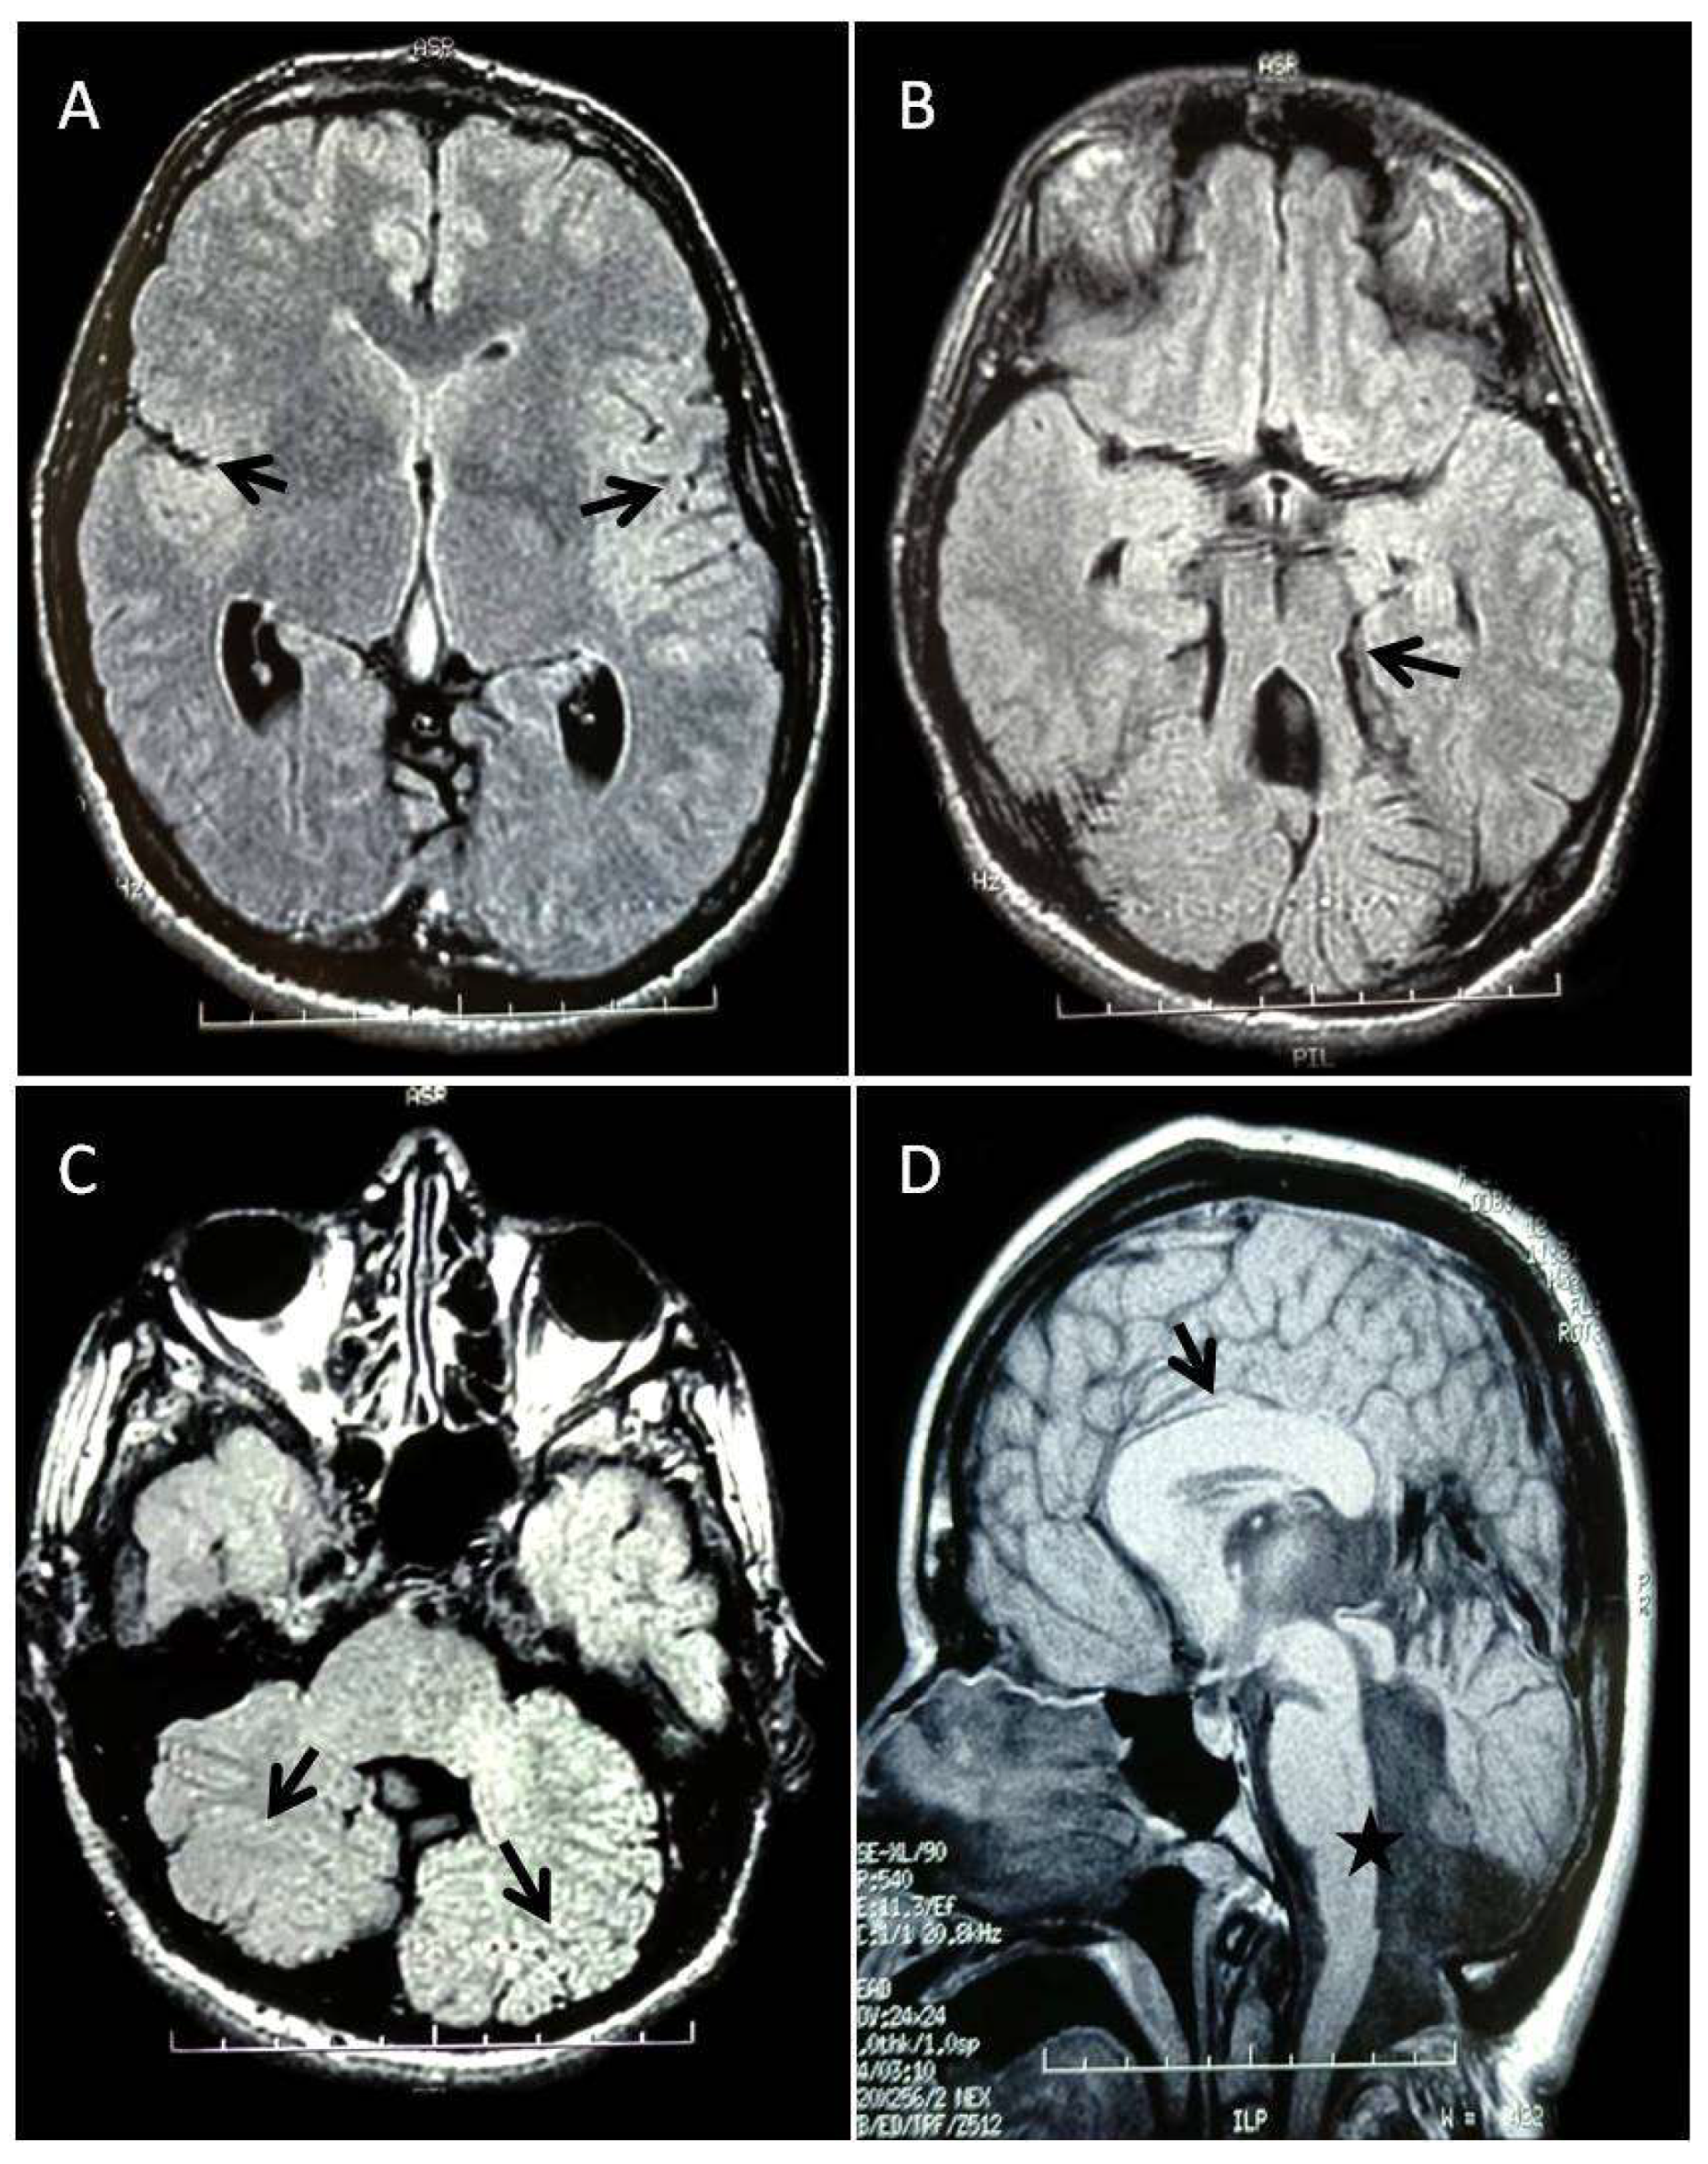

| JS | Joubert syndrome |

| MTS | Molar tooth sign |

| MRI | Magnetic resonance imaging |

| ACC | Agenesis of the corpus callosum |